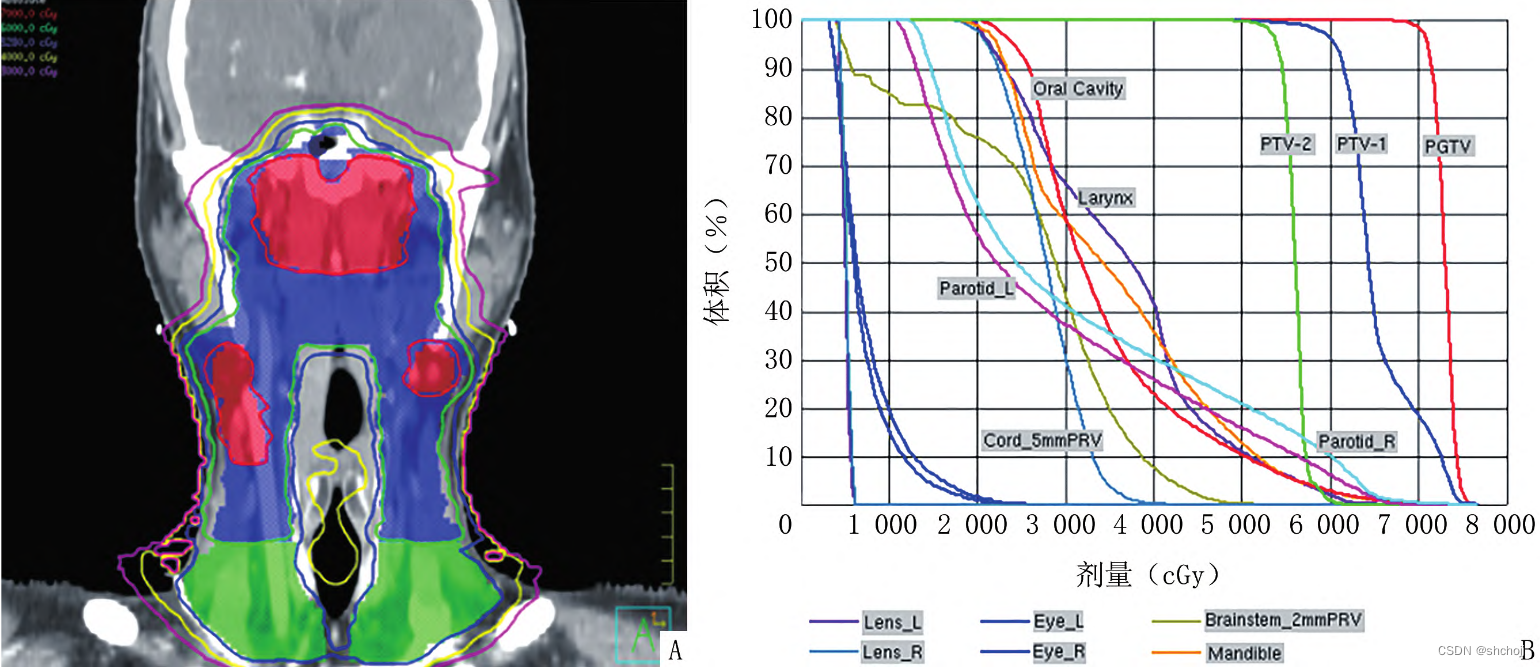

剂量体积直方图(dose volume histogram,DVH):

- 一维剂量度量为可接受一定剂量照射的器官体积,或一定体积的照射剂量

- 二维剂量刻度为DVH曲线上点代表剂量或者体积的绝对值(Gy/cc)和相对值(%)

- DVH不能提供剂量的三维空间分布,而定位CT上三维图像可以显示某等剂量曲线相对于OAR的空间分布。

同步加量技术(simultaneous integrated boost,SIB):在头颈及胸腹部恶性肿瘤放疗中得到广泛应用,主要优势在统一计划内针对不同区域给予差异性剂量分配。SIB计划评估与常规IMRT计划评估类似,关键在与确认不同梯度处方剂量均能满足治疗需求。

三维剂量分布:不同轴面逐层分析;

审计各靶区是否按照预设剂量分布覆盖,并达到预期目标

正常组织所受剂量的范围及空间分布

PTV:处方剂量覆盖。

CTV、GTV:易复发

OAR:PTV外处方剂量保护

- DVH评估OAR受量